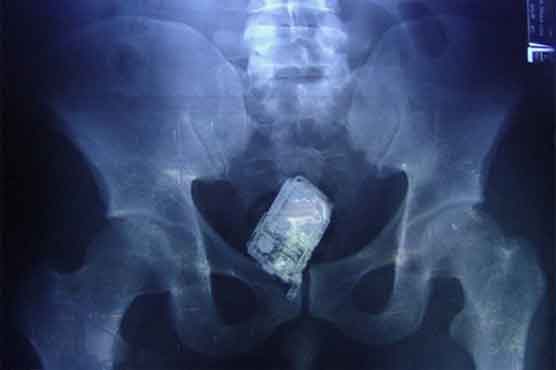

Summary X-ray showed mobile phone hidden inside the colon of the prisoner.

COLOMBO: A Sri Lankan prisoner who tried to hide his mobile phone during a search of his cell was caught out when guards heard ring tones from his rear-end, a hospital official said Friday.

The 58-year-old convict had to be admitted to the national hospital in Colombo where doctors later retrieved the handset from his rectum.